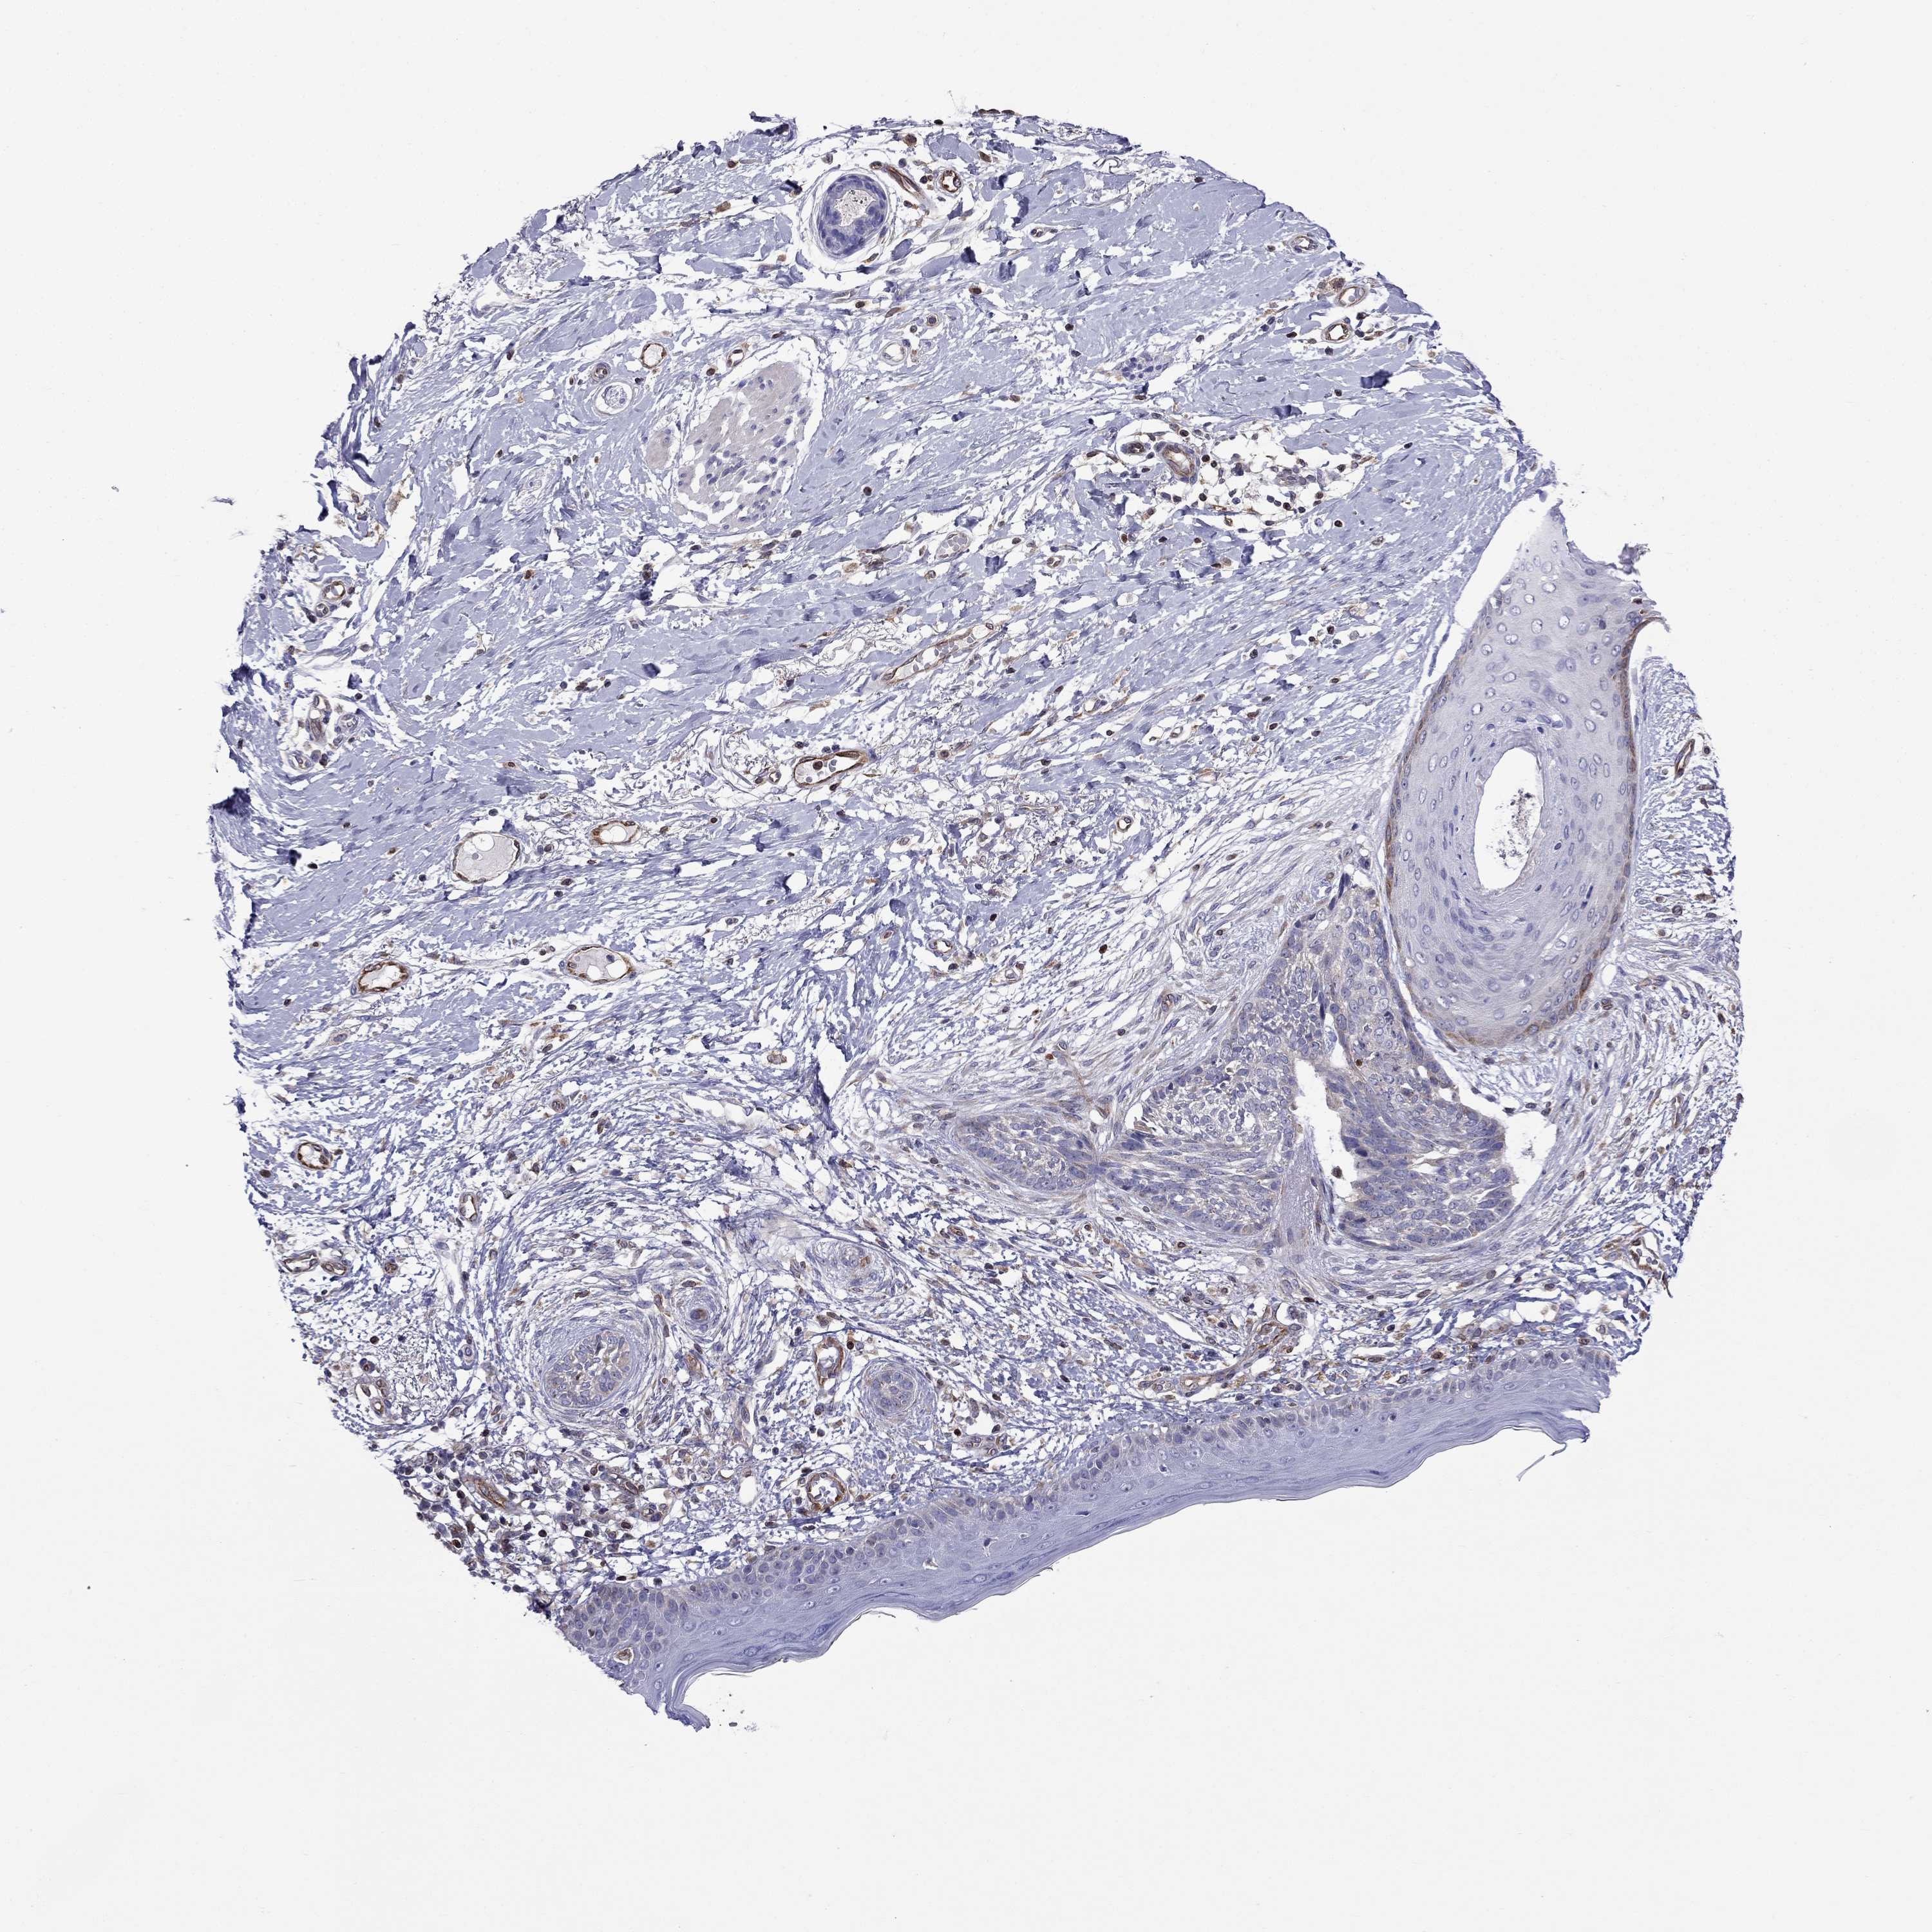

SKIN CANCER - Protein expressioni

A mouse-over function shows sample information and annotation data. Click on an image to view it in a full screen mode. Samples can be filtered based on level of antibody staining by selecting one or several of the following categories: high, medium, low and not detected. The assay and annotation is described here.

Antibody stainingi

Antibody staining in the annotated cell types in the current human tissue is reported as not detected, low, medium, or high, based on conventional immunohistochemistry profiling in selected tissues. This score is based on the combination of the staining intensity and fraction of stained cells.

Each image is clickable and will lead to virtual microscopy that enables deeper exploration of all samples and also displays staining intensity scores, fraction scores and subcellular localization as well as patient and tissue information for each sample.

Antibody HPA051160

Staining

High

Medium

Low

Not detected

Intensity

Strong

Moderate

Weak

Negative

Quantity

>75%

75%-25%

<25%

None

Location

Nuclear

Cytoplasmic/membranous

Cytoplasmic/membranous,nuclear

Basal cell carcinoma

Squamous cell carcinoma, NOS